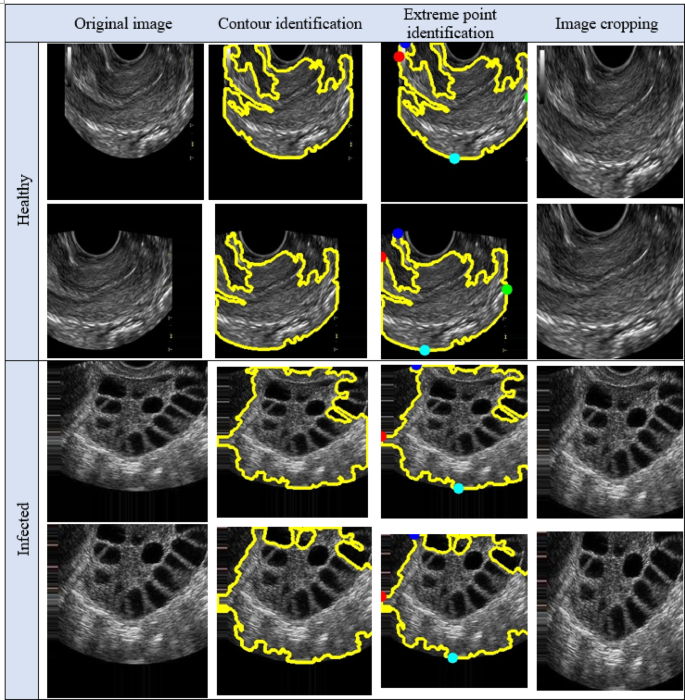

The labelled PCOS ultrasound images subjected to image cropping by finding the biggest contour and extract the extreme points to form the crop images. The image cropping was performed in order to focus on the significant image features. The cropped images are performed with data augmentation that 14 images for each image in the dataset resulting with 53,200 images. All the data augmented images are subjected to enhance the brightness of the image by forming Histogram equalized image, CLAHE image and Fuzzy Contrast Enhanced image. This work forms both Histogram equalized image and CLAHE with the intent of performance evaluation as both of them serves a distinct purpose. The normal Histogram equalization of the image works for the entire image by stretching the pixel intensity. Though CLAHE is a method of histogram equalization, it applies histogram for small adaptive regions that prevents noise in homogenous areas. The FCE images, known for their high brightness, are validated using the PSNR ratio and processed through the Fuzzy Contrast Enhanced module. The FCAU-Net framework, depicted in Fig. 5, uses these FCE images as input. The images are passed through four encoder blocks and four decoder blocks. The encoder-decoder feature maps are combined using the Feature Fusion Context (FFC) module, which extracts positional and contextual characteristics to generate optimized fused feature maps.

After labeling, the image cropping was done to form the cropped image. The results of the PCOS Ultrasound images before and after Image cropping are shown in Fig. 10. The cropped PCOS Ultrasound images are subjected to data augmentation to form 14 images for each image resulting with 53,200 images data augmented cropped images. The results obtained from the data augmented PCOS infected and normal healthy ultrasound images are shown in Figs. 11 and 12 respectively.